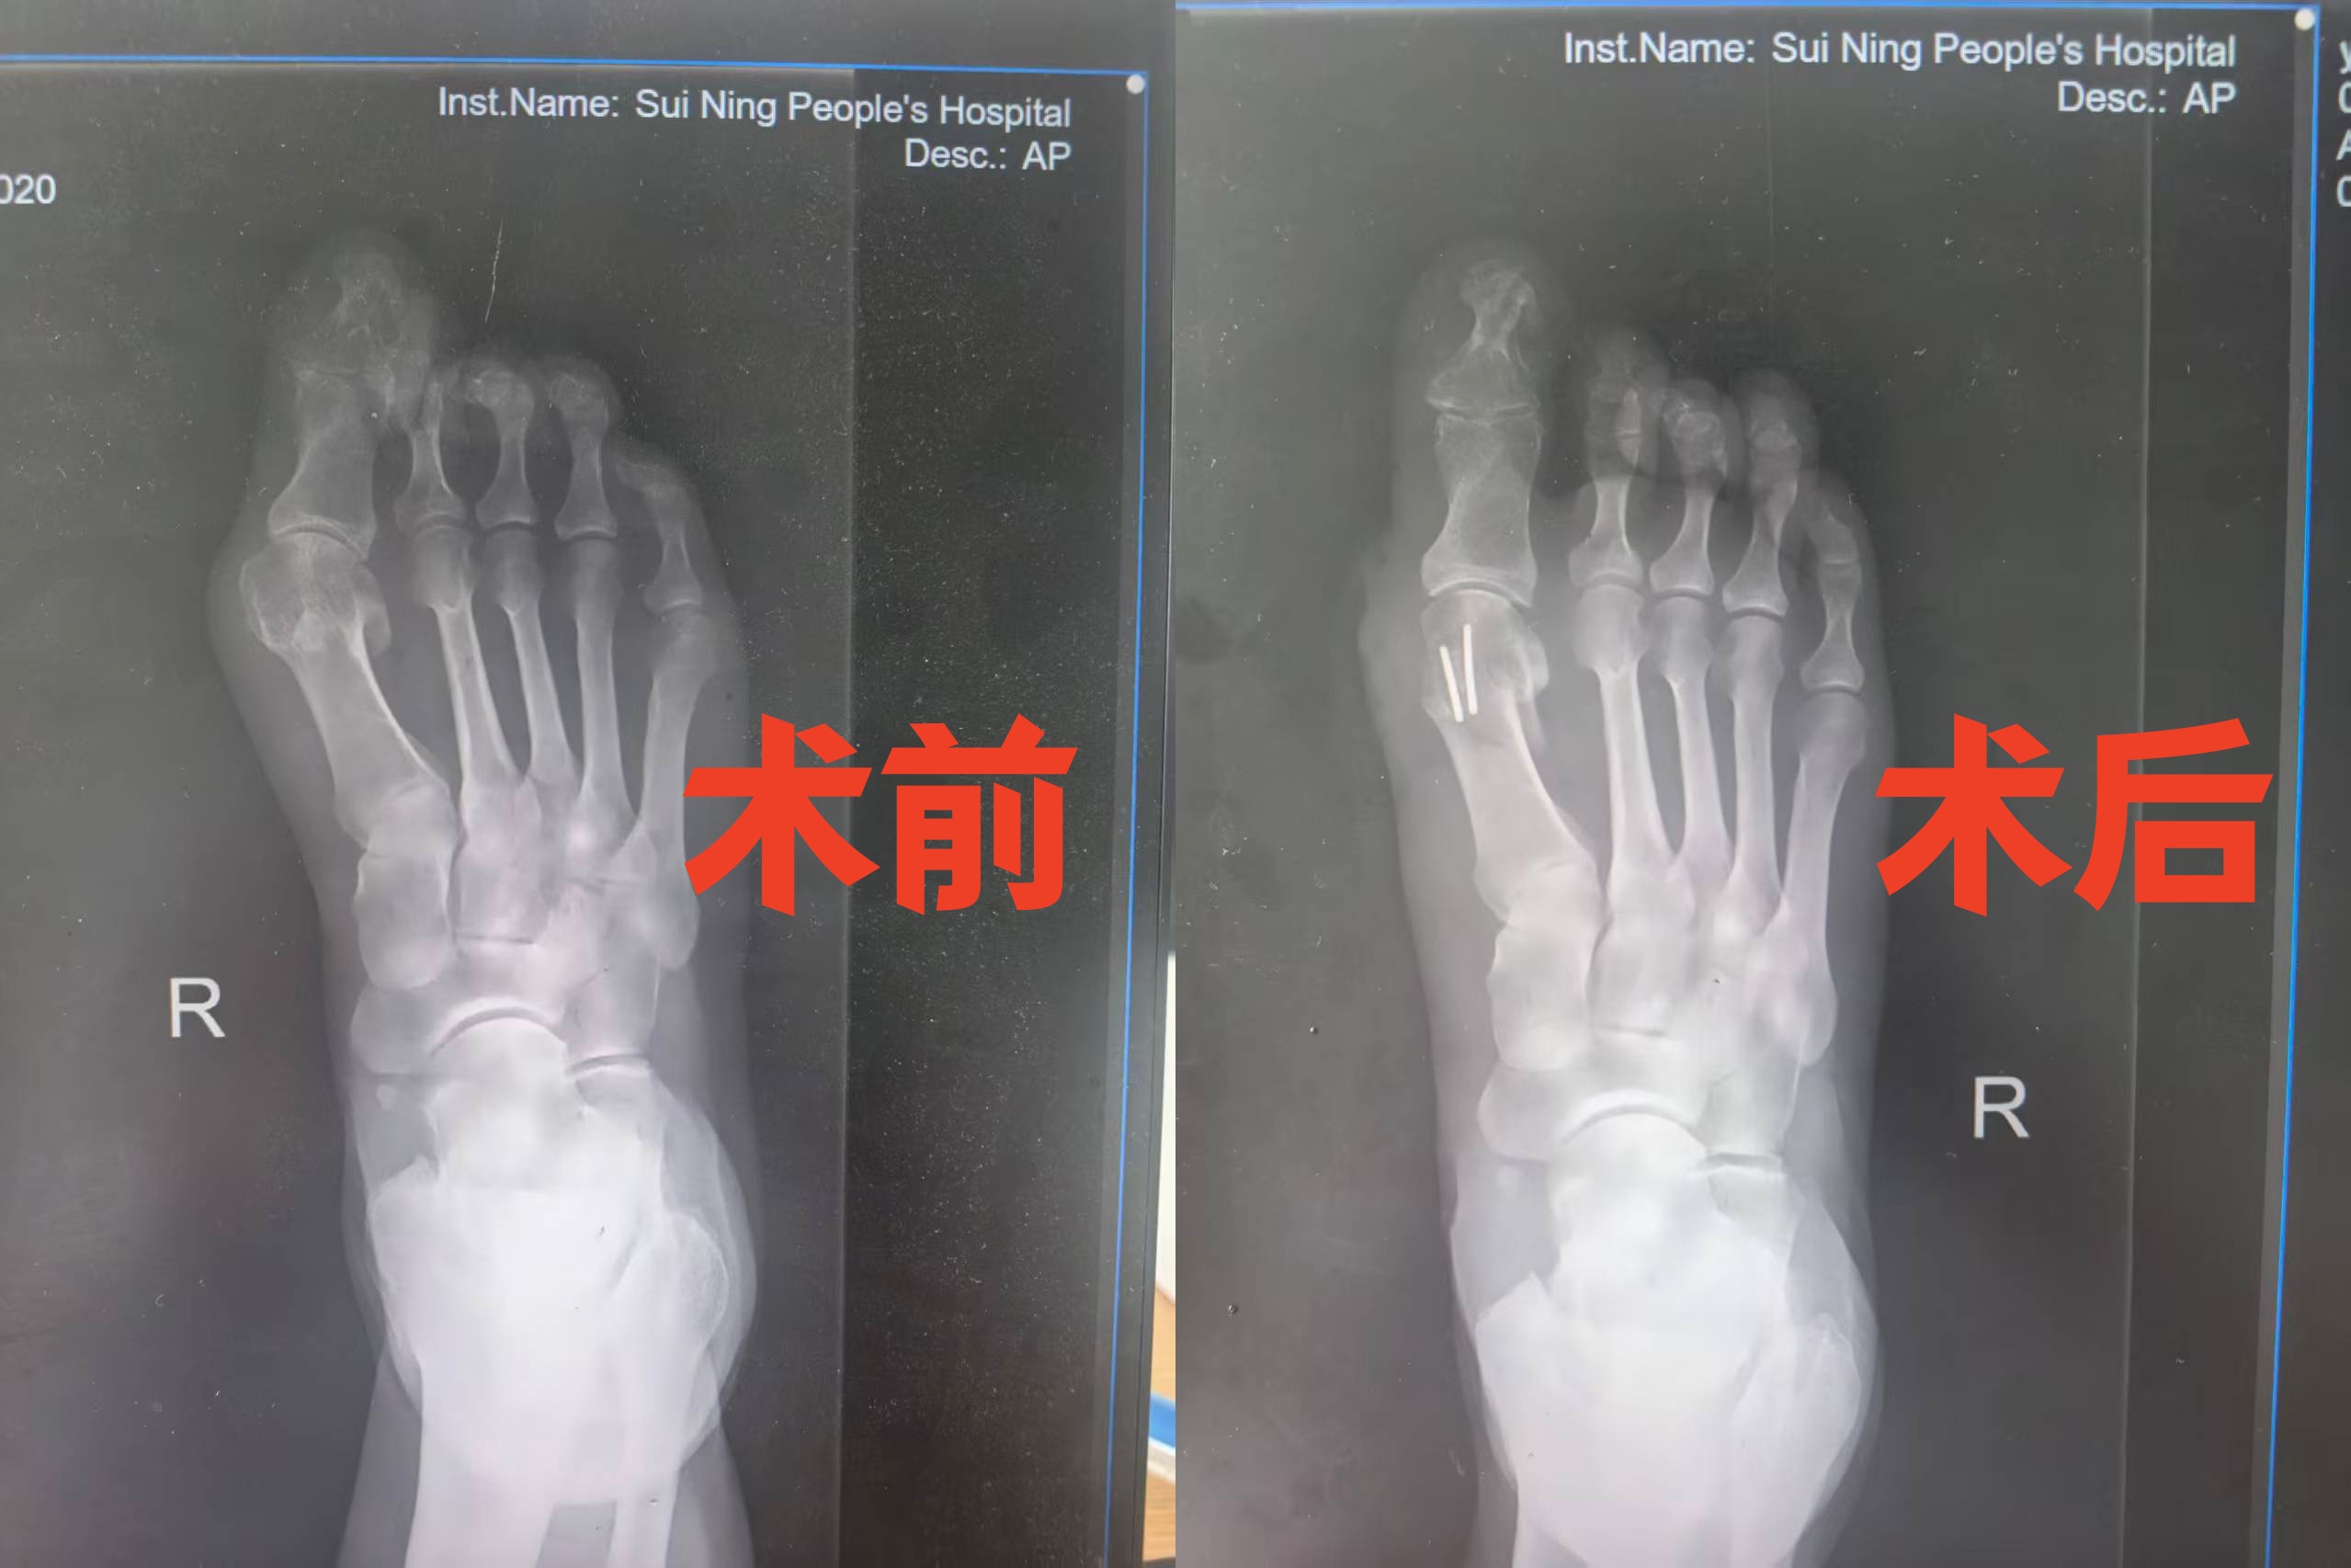

为了解决这个多年困扰,近日王先生来到我院骨科就诊,医生接诊后,详细询问王先生的病史,对其进行全面查体,并安排X线检查进一步确诊。检查结果显示,王先生为先天性足踇外翻,双足均为重度踇趾外翻,其中右侧症状更为显著,还伴有关节内侧突出等表现,符合手术指征。结合王先生的年龄、症状表现、影像学检查结果及生活需求,医生经过综合评估,为其制定了个性化的右足踇趾外翻微创矫正手术方案,并向王先生及家属详细讲解了手术流程、优势及术后注意事项,消除了他们的顾虑。

手术当日,在科主任杨春生的带领下,手术团队默契配合,严格按照术前设计方案精准操作。与传统手术相比,此次微创矫正手术优势凸显:仅在患者右足留下一个2厘米的微小切口,有效避免了传统手术大切口带来的创伤;术中借助实时透视技术,精准完成截骨与矫形固定,全程操作精细、高效,仅用30分钟便顺利完成手术。术后,患者足部畸形得到明显矫正,疼痛瞬间缓解,且手术创伤小、出血少,最大程度保留了足部的美观度,术后并发症发生风险极低。